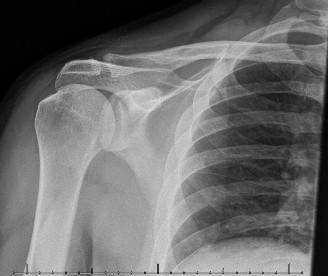

The patient undergoes resection arthroplasty with antibiotic cement spacer and a 6-week course of IV antibiotics. He returns to clinic 4 months later with improved pain, CRP <3, however, on examination he has a positive belly press sign and increased external rotation compared with the contralateral shoulder. Imaging is shown in Figure 2–57.

Figure 2–57

The correct answer is (D). The patient has completed his course of antibiotics and his spacer and is now an appropriate candidate for explanation of the cement spacer with revision shoulder arthroplasty, therefore Choices A and C are incorrect. The patient’s clinical examination findings point to rotator cuff tear (specifically subscapularis) which has occurred in the interval between his obtaining his initial total shoulder arthroplasty and his current examination. Therefore, total shoulder arthroplasty (Choice B) is contraindicated, and the patient should have a reverse total shoulder arthroplasty. Objectives: Did you learn...? Recognize the clinical presentation of a patient with infection after total shoulder arthroplasty?